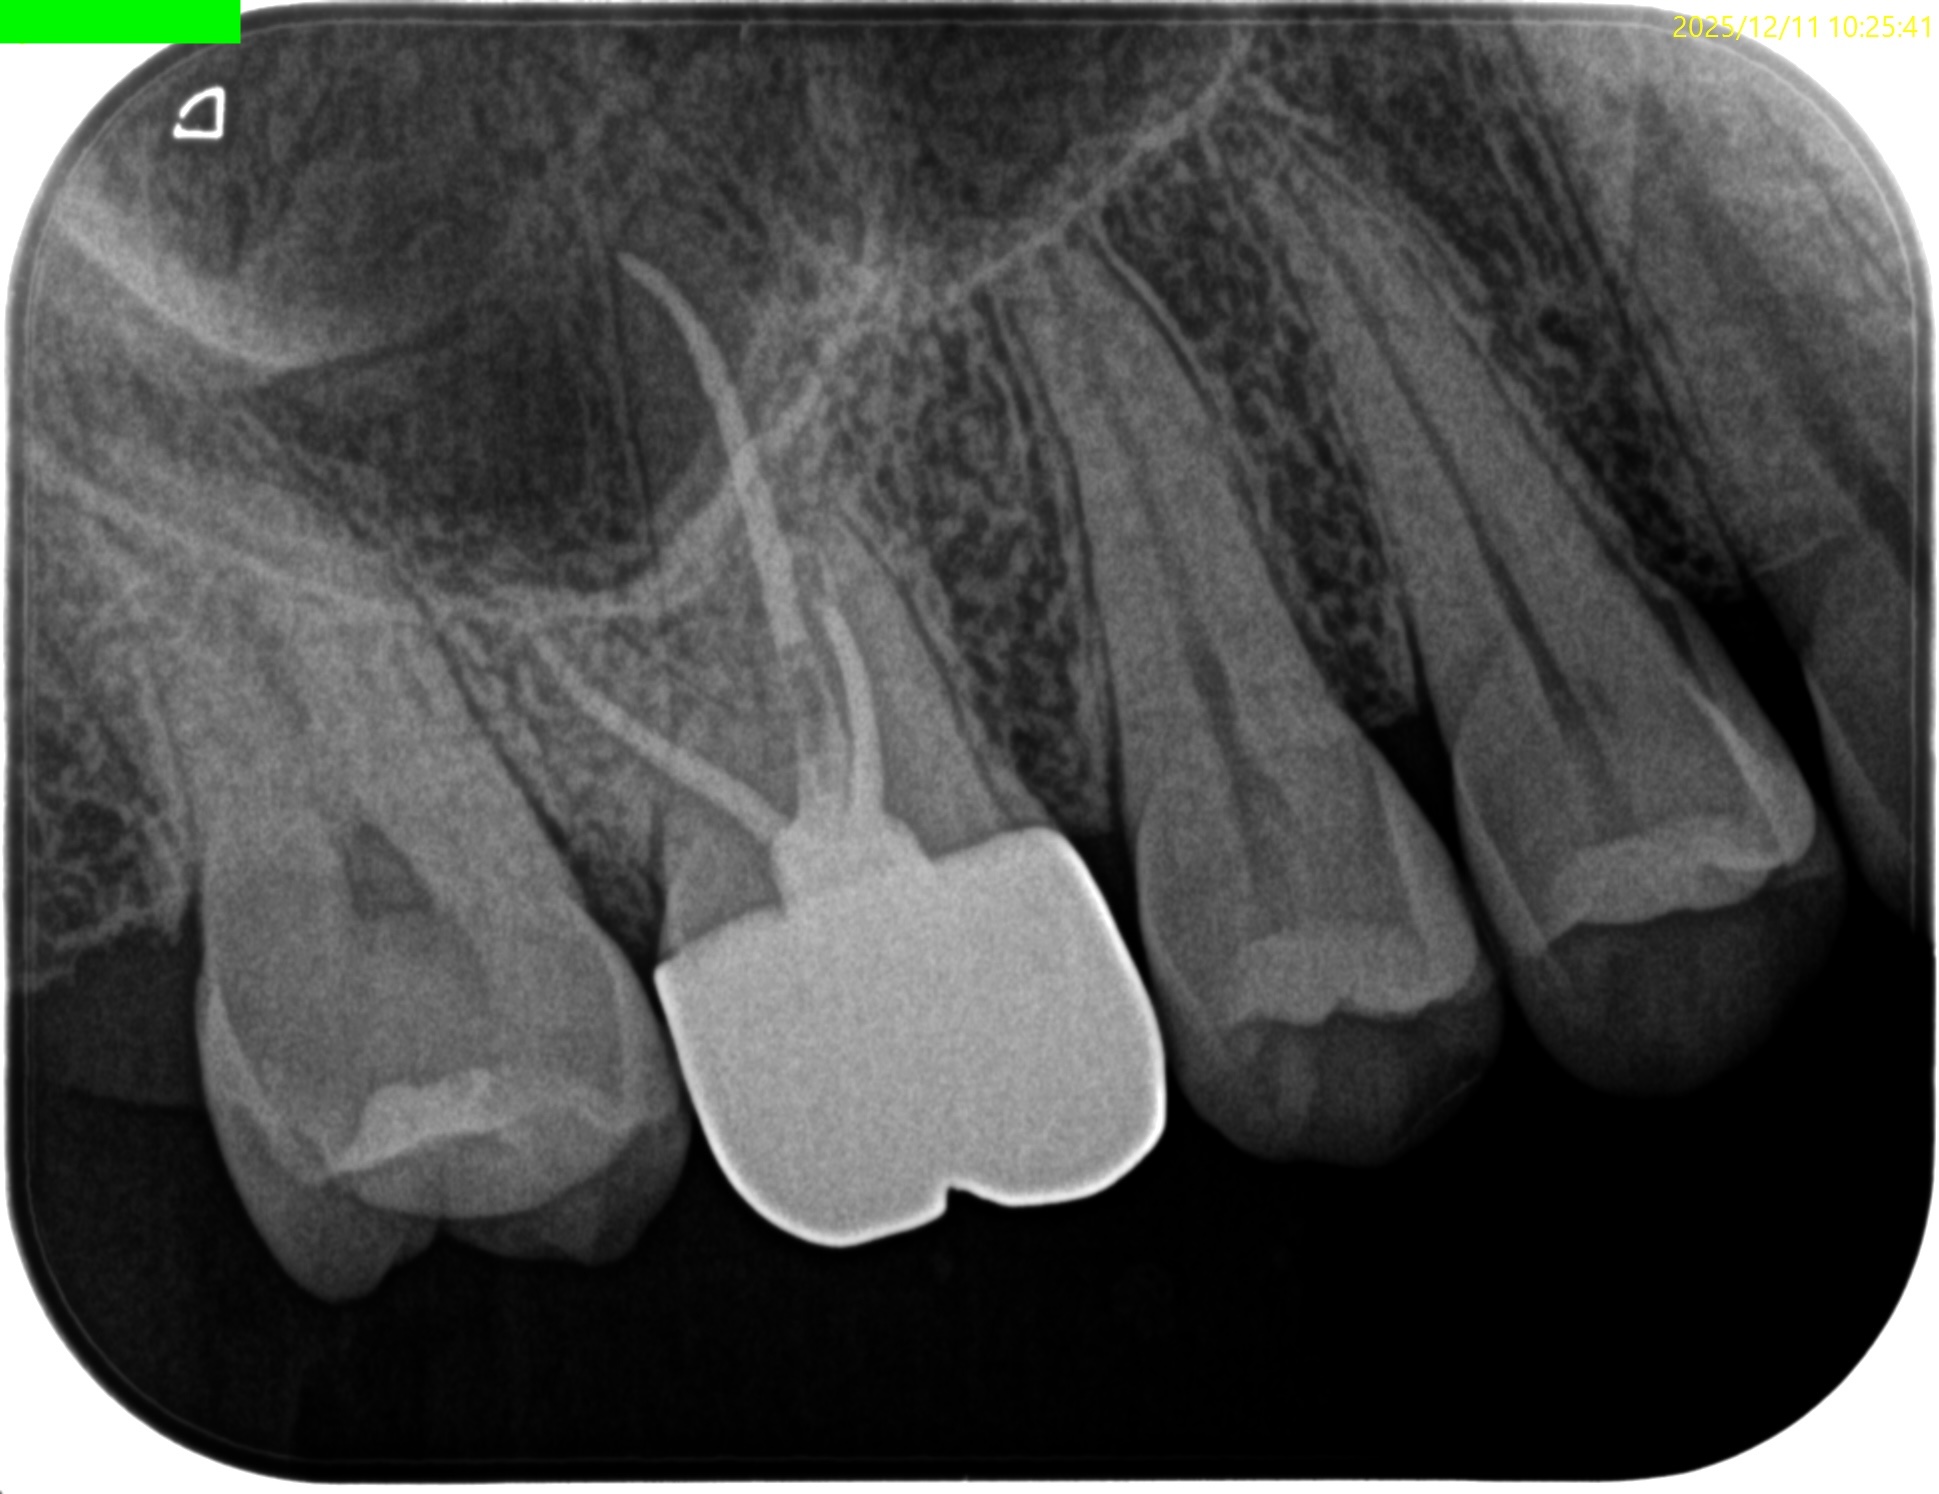

#3 RCT 1yr recall(2025.12.11)

PA, CBCTも撮影した。

初診時と比較した。